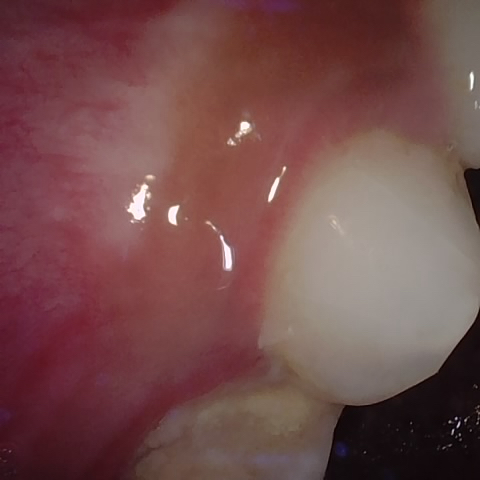

Annotated as "Good"